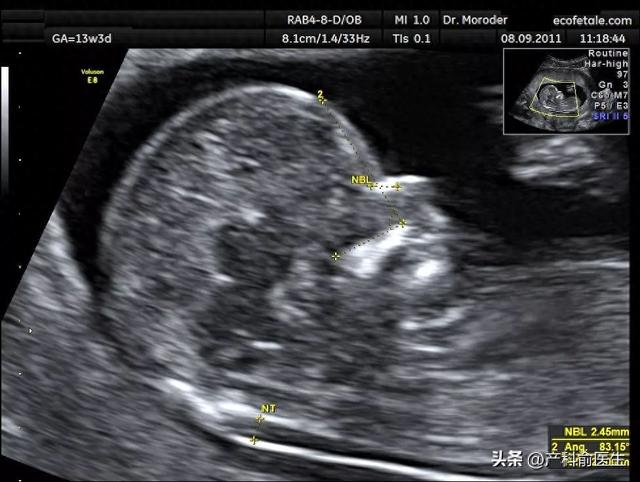

男孩女孩nt值区别(NT检查真能辨别胎儿性别揭秘医学真相)

网络上流传着一种说法:"通过NT检查(颈项透明层检查)可以判断胎儿性别"。许多宝妈宝爸看到这类消息后,既好奇又困惑——这项产前筛查项目,怎么就突然和胎儿的性别鉴定扯上了关系?今天俞医师就用最直白的方式,揭开NT检查的...